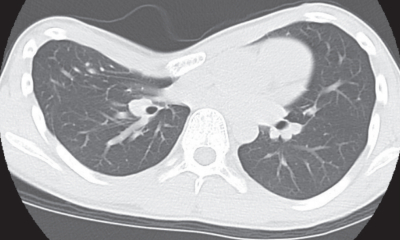

体温 36.8 ℃。脈拍 84/分、整。血圧120/68 mmHg。呼吸数 18/分。SpO₂ 98 %(room air)。胸骨陥凹があり呼吸性に変動しない。皮膚の発赤、腫脹および熱感はない。胸部に圧痛を認めない。心音と呼吸音とに異常を認めない。胸部単純 CTを別に示す。

漏斗胸は胸骨が後方に陥没して胸郭が内側に窪む状態を指し、発育中に徐々に目立ってくることが一般的。

この状態は、健康に影響を与えることは少ないが、外見による心理的な影響が大きい。